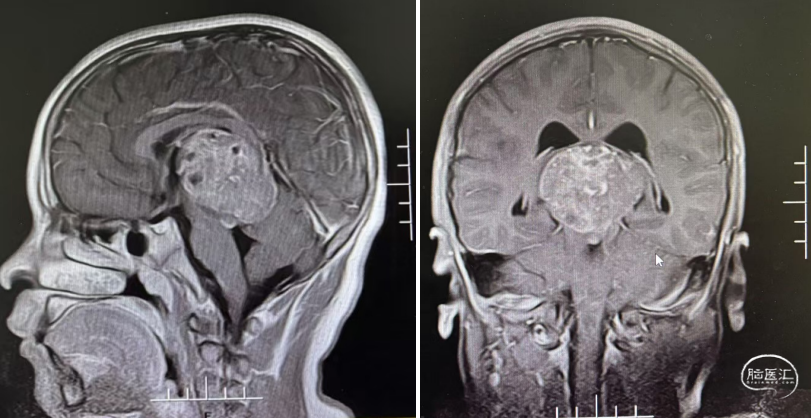

头部CT显示:鞍区-鞍上区-双侧额叶-胼胝体前份可见一不规则形囊实性肿块,实性部分密度稍高,平扫CT值约39HU,冠状位最大层面约55mm×36mm,平扫CT值约39-15HU,周围脑实质可见片状低密度水肿密度,双恻脑室前角受压,中线结构无移。

头部MRI显示:鞍区-鞍上区-双侧额叶-胼胝体前份可见一不规则形等-长T1等-长T2信号囊实性团块灶,FLAIR呈等-稍高信号,DWI示实性部分稍高信号,相应ADC低值,增强扫描病灶实性部分明显强化;邻近脑实质见片状FLAIR高信号,双侧侧脑室前角受压,中线结构无移位,脑沟、脑裂未见明显增亮。松果体区见环形强优结节,直径约9mm。

经儿童脑肿瘤MDT讨论后,建议先化疗再放射治疗。1疗程后病变明显退缩,甲胎蛋白(AFP)、人绒毛膜促性腺激素(β-HCG)降至正常范围。结疗后复查,肿瘤完全消失,无复发。此后1年予以定期复查未见复发。

1疗程后评估